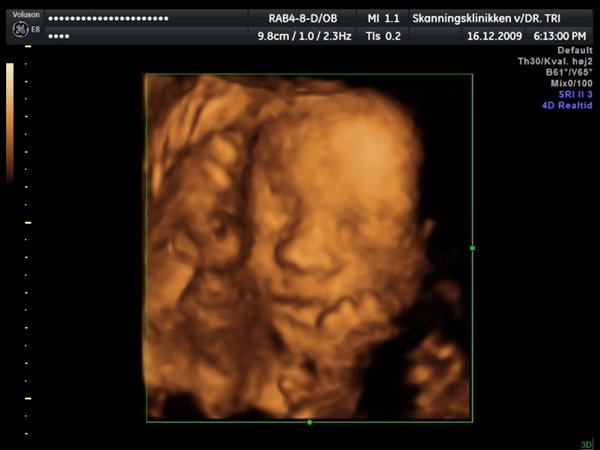

Ja, så var vi til 3D scanning med Ida igår. Og hvad kan jeg sige andet end hun er en meget træt pige

Jeg tror vi talte hun gabte mellem 10 og 11 gange under hele scanningen. Derudover havde hun meget travl med at gemme sig bag sine hænder som hun hele tiden åbnede og lukkede så det så ud som om hun vinkede

Billederne blev ikke så gode som jeg havde håbet, for lige som sin bror ligger hun meget tæt på moderkagen og med navlestregnen forand hovedet. Men de er ok, vi kan da se at hun ser sund og rask ud og at hun trives derinde.

Vedhæftede fotos (klik for at se i fuld størrelse)